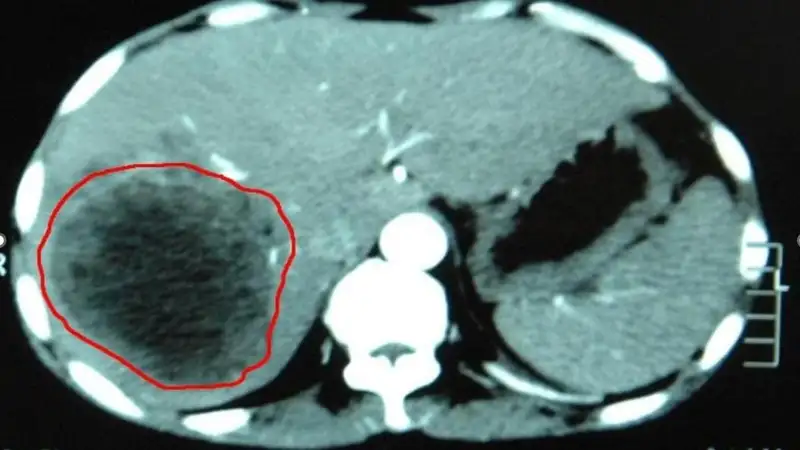

"По словам лечащего врача Ерасыла Арапова, заведующего отделением торакоабдоминальной хирургии Жамбылского многопрофильного центра онкологии и хирургии, женщина поступила в стационар уже на грани начала необратимого процесса. Новообразование занимало 70% всей печени, тесно связываясь с желчным пузырем и общей печеночной артерией, а вес гигантской опухоли составлял шесть кг. Она сдавила полую вену, желчный пузырь с протоками и крупные сосуды печени, полностью поглотив её правую долю", – говорится в сообщении.

Хирурги удалили у женщины практически всю правую долю печени, желчный пузырь, провели резекцию лимфоузлов воротной вены и общей печеной артерии. Дополнительная сложность заключалась в необходимости выделения почти вслепую нижней полой вены и общего желчного протока.